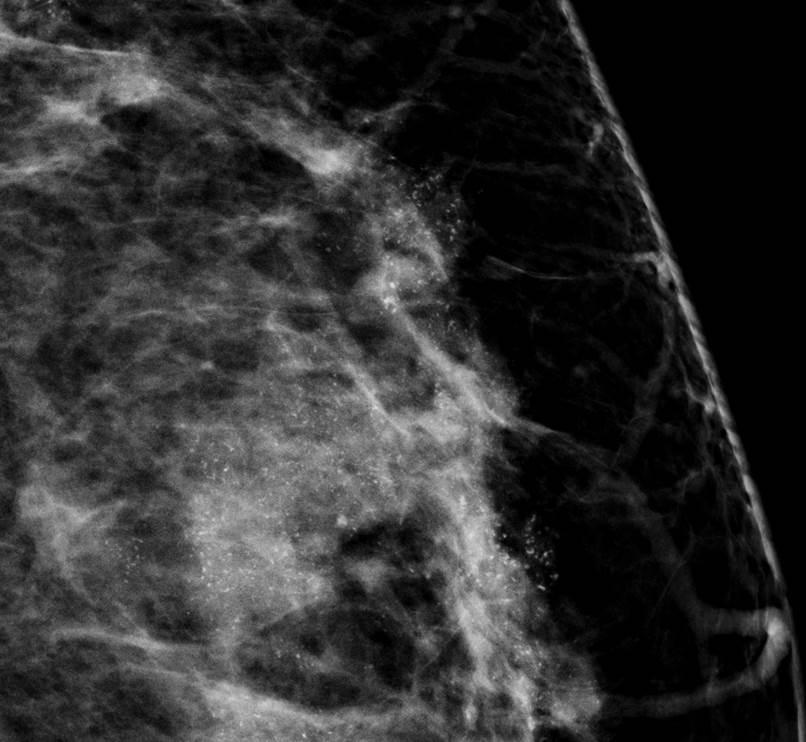

Ung thư vú

Ung thư vú - Ảnh 4

» Thông tin: Nữ giới – 42 tuổi.

» Lâm sàng: Kiểm tra sức khỏe.